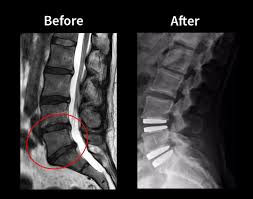

Disc Replacement Surgery, also known as Artificial Disc Replacement (ADR), is designed to remove a damaged intervertebral disc and replace it with a prosthetic implant that preserves spinal motion. Unlike spinal fusion, which restricts movement at the operated segment, disc replacement maintains biomechanical flexibility. Consequently, it reduces stress on adjacent spinal levels and lowers the risk of accelerated degeneration.

Disc Replacement Surgery, also known as Artificial Disc Replacement (ADR), involves removing a diseased intervertebral disc and replacing it with a prosthetic implant. This implant is designed to replicate natural disc motion and absorb mechanical loads efficiently. Consequently, spinal alignment and flexibility are maintained.

During the procedure, the surgeon carefully accesses the affected spinal level. After removing the degenerated disc material, the artificial disc is positioned precisely between the vertebrae. Intraoperative imaging confirms alignment and stability before closure. As a result, spinal biomechanics are restored without fusing the vertebrae together.

Artificial discs typically consist of metal endplates and a synthetic core that allows controlled movement. Therefore, the implant permits flexion, extension, and rotational motion similar to a natural disc. Unlike fusion, which permanently limits movement at one segment, disc replacement maintains spinal mobility. At Dr. Kakani’s clinic, patient selection is performed meticulously. Consequently, only individuals who meet strict eligibility criteria are recommended for this procedure, ensuring safety and long-term effectiveness.

Disc Replacement vs. Spinal Fusion

Spinal fusion historically served as the primary surgical treatment for degenerative disc disease. While fusion stabilizes the affected segment, it eliminates motion between the vertebrae. Consequently, mechanical stress shifts to adjacent spinal levels, potentially accelerating degeneration over time.

In contrast, disc replacement preserves motion at the treated level. Therefore, natural spinal biomechanics are maintained. Furthermore, maintaining movement reduces adjacent segment overload and may decrease long-term complications. Although both procedures have specific indications, disc replacement offers advantages in selected patients. Recovery may also be faster due to preserved mobility. However, proper patient selection remains critical. At Dr. Kakani’s Brain Spine & Dental Super Speciality Clinic, detailed consultations ensure that the most appropriate surgical option is chosen based on individual spinal pathology.